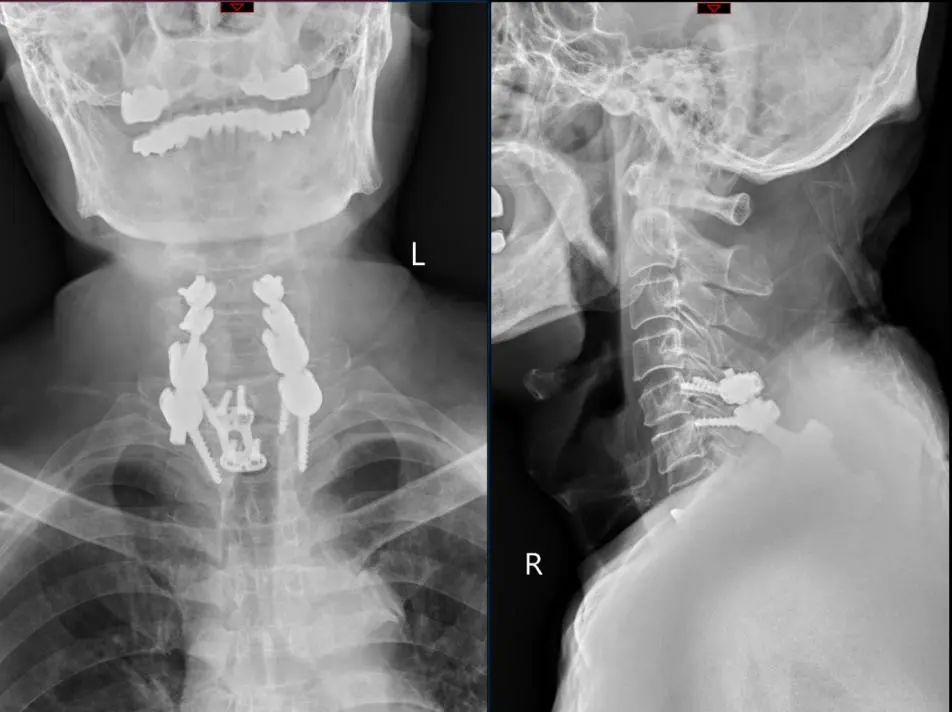

经过颅骨牵引后,在孙欣副主任的带领下,团队成员彭智恒博士、李广盛博士、黄维渊博士以及程龙医师在充分研究患者骨折脱位情况,结合患者身体条件,为患者实施了颈椎前路加后路联合手术。该部位手术难度极大,术中由于肩关节遮挡,术中DR难以准确指示胸1、胸2椎体置钉位置,需要术者全凭手感置钉。孙欣副主任凭借丰富的手术经验,加上麻醉科、手术室团队的密切配合,手术十分顺利。术后复查显示脱位的颈椎已完全复位,同时未造成神经功能二次损伤。

术后复查颈椎DR